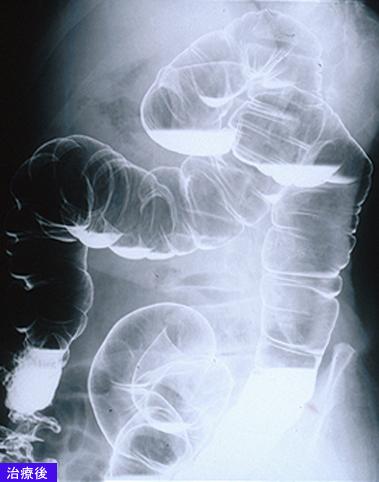

A case of MLP (multiple Lymphomatous Polyposis) type malignant lymphoma which involved the G1 tract including the esophagus.

Malignant Lymphoma/MLP type

Large intestine(Colon)/More than one of the above

X-ray